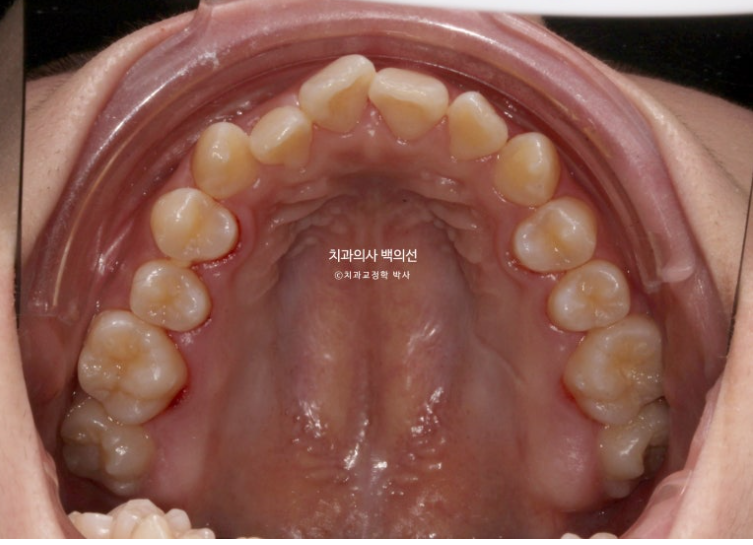

24.01

23년 10월부터 24년 1월까지 악궁확장 후 모습입니다.

악궁확장이 성공하면 앞니 사이가 벌어지죠.

이틈은 사진처럼 몇주내에 자연스럽게 다시 닫히게 됩니다.